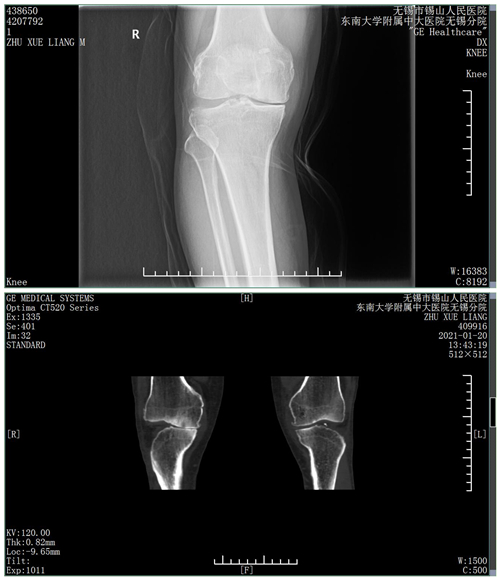

困扰患者朱先生的右膝关节疼痛已有3年,严重影响到他正常行走。在我院骨科门诊,骨科副主任倪英杰结合相关检查,明确诊断为“右膝关节单间室骨关节炎”,立即安排他入院手术治疗。

术前,倪英杰主任在科内组织了术前讨论,针对患者的病情制定了个性化手术方案。该患者右侧膝关节为内侧间室病变,而外侧间室、交叉韧带等结构相对较好,选择什么样的术式直接决定患者术后的生活质量。针对该疾病,此前骨科采用的全膝关节置换术,需将整个膝关节的关节面进行截骨,切除过多正常的骨质、交叉韧带和半月板,创伤较大。结合患者年龄、症状、体征及术前影像学检查等,骨科医疗团队最终决定为患者实施技术难度更大的膝关节单髁置换术。